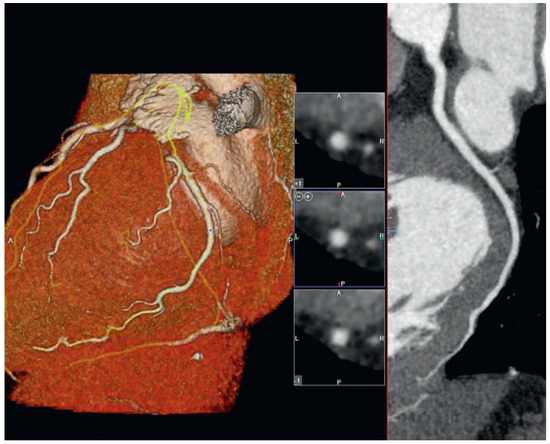

Five-Year Prognosis in Patients with Normal Coronaries Arteries

by Damien Casagrande, Jean-Jacques Goy, Laurent Poncioni, Robert Androux, Mario Togni and Stéphane Cook

Cardiovasc. Med. 2016, 19(4), 117; https://doi.org/10.4414/cvm.2016.00405 - 20 Apr 2016

Objectives: The aim of this study was to assess the 5-year prognostic value of multidetector coronary computed tomography angiography (CCTA) in patients with normal coronary arteries. Background: Use of CCTA is increasing in patients with suspected coronary artery disease. Although there is [...] Read more.

Objectives: The aim of this study was to assess the 5-year prognostic value of multidetector coronary computed tomography angiography (CCTA) in patients with normal coronary arteries. Background: Use of CCTA is increasing in patients with suspected coronary artery disease. Although there is a large body of data supporting the prognostic role of CCTA for major adverse cardiac events in the long-term prognostic the role in patients with normal coronary arteries is still partially unknown. Methods: Between April 2005 and March 2007, 506 consecutive patients (313 men) were studied with CCTA in order to detect the presence of coronary artery disease. Patients were classified as having strictly normal coronary arteries versus abnormal coronary arteries (plaques, calcified and obstructive coronary arteries). Patients with strictly normal coronary arteries were followed up for 5 years, for the occurrence of: (1) cardiac death, (2) nonfatal myocardial infarction, (3) unstable angina requiring hospitalisation, and (4) revascularisation. Results: Two hundred patients (124 men, mean age 64 ± 27 years) were enrolled and subsequently followed up for exactly 5 years after the initial investigation. Pretest probability was 25 ± 15% in the total population and 13 ± 4% in the 200 studied patients. During this follow-up 2 patients (1%) died from noncardiac causes (1 sepsis and 1 chronic obstructive pulmonary disease), 1 patient underwent percutaneous atrial septal defect closure (0.5%) and 1 patient (0.5%) experienced nonfatal endocarditis. Acute coronary syndrome, myocardial infarction or stable angina pectoris did not occur during this follow-up. A total of 196 patients were free of adverse events (98%). Conclusions: CCTA provides important prognostic information in patients with normal coronary arteries showing excellent long-term prognosis without coronary events. Full article